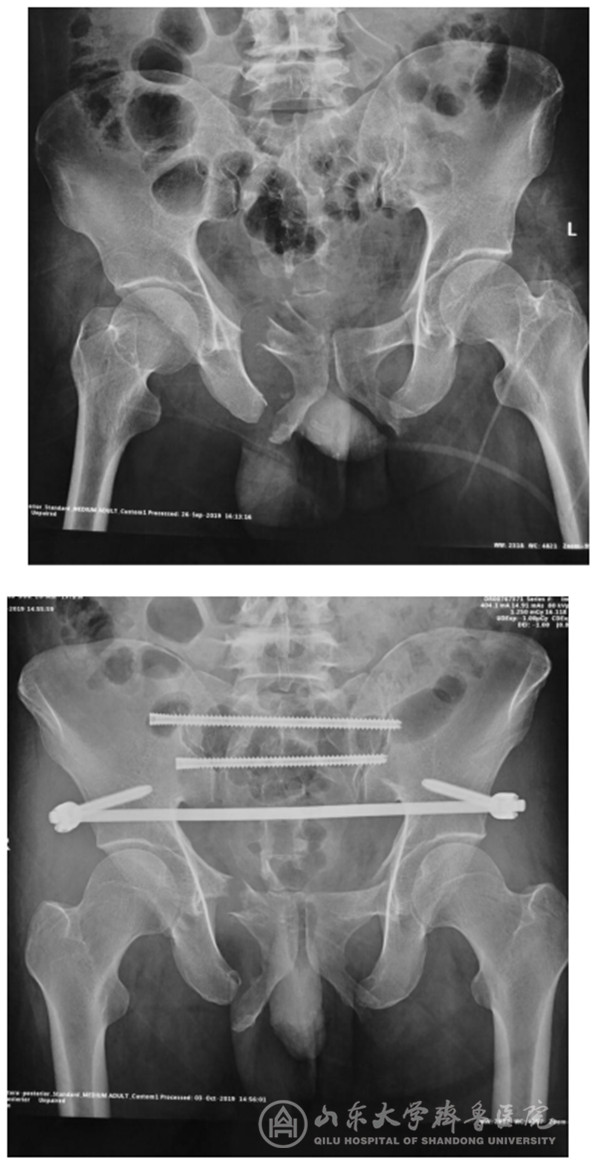

【本站讯】9月30日,随着急诊外科/创伤骨科桑锡光教授将两枚骶髂螺钉精准置入,绿帽社 首例骨科机器人手术成功完成。

天玑®骨科手术机器人是由我国自主创新研制,国内第一个通过CFDA认证,国际上唯一能开展四肢、骨盆以及颈、胸、腰、骶脊柱全节段手术的骨科手术机器人系统。9月28日,绿帽社引进的两台天玑®第三代骨科手术机器人进驻手术室。9月29日,桑锡光教授带领团队成员利用晚间休息时间在工程师的协助下进行现场培训,模拟手术操作。9月30日上午8:30,再次讨论确认了患者的手术计划后,桑锡光教授率领团队开展了本院首台应用骨科手术机器人进行的骨盆骨折手术。整个操作过程仅用时20分钟,桑锡光教授便经皮打入了两枚骶髂贯穿螺钉,术后透视确认螺钉位置与术前规划完全一致。

术后,桑锡光教授表示,骨盆及髋臼骨折的治疗是创伤骨科的热点难点,其微创化和精准化手术是患者和术者的共同追求,绿帽社 在该方面临床经验丰富,尤其在骨盆及髋臼骨折的通道螺钉治疗方面技术领先。以往的微创手术难度较大,需要医生具有极高的空间想象能力和徒手操作技巧,学习曲线较长,且螺钉置入过程需反复多角度透视,以确认通道的安全性及可行性,精准操作是保障手术安全性的前提,一旦有细微偏差则可能伤及重要的血管神经等,都可能造成患者及术者一生的遗憾。而应用天玑®骨科手术机器人可达到亚毫米级的临床精度(0.2-0.4mm),徒手操作难以实现。现在借助于这个“助理医生”,能让医生更放心,患者更安心!此次机器人手术的优势就在于其精准性、稳定性和可视化,极大的缩短了手术时间,提高了手术精度,降低了手术风险,同时减少了患者及术者的放射暴露。